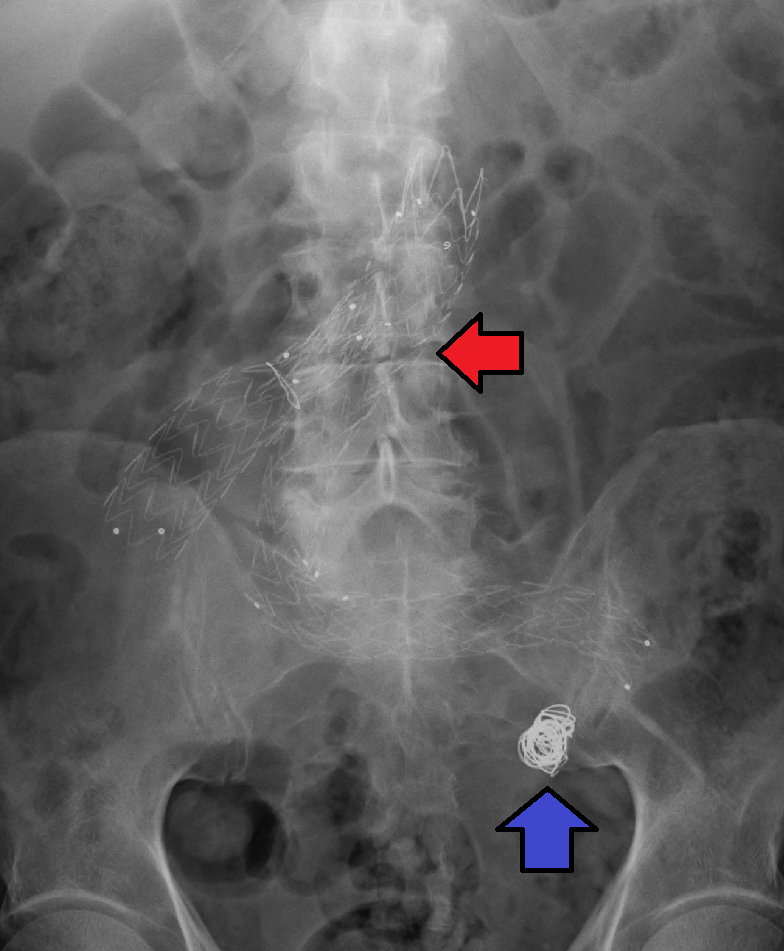

뇌동맥류 치료에는 현재 두 가지 방법이 있다. 수술적 클리핑과 혈관내 코일링이다. 수술적 클리핑은 1937년 존스홉킨스 병원의 월터 댄디가 도입한 방법으로, 개두술을 통해 뇌동맥류를 노출시키고 클립으로 뇌동맥류의 기저부나 경부를 막는 것이다. 혈관내 코일링은 1989년 이탈리아 신경외과 의사 구이도 구글리엘미가 UCLA에서 도입한 방법으로, 사타구니의 대퇴동맥을 통해 카테터를 뇌동맥류까지 통과시켜 백금 코일을 삽입하여 혈전을 형성시켜 뇌동맥류를 채우는 방식이다.[42] 어떤 치료법이 더 적절한지에 대해서는 논쟁이 계속되고 있다.[41]

대동맥, 팔, 다리, 머리의 동맥류는 혈관의 약화된 부분을 우회 접합 이식편으로 대체할 수 있다. 덜 침습적인 혈관내 기술로는 다리의 동맥을 통해 덮개가 있는 금속 스텐트 그래프트를 삽입하여 동맥류 전체에 걸쳐 배치하는 방법이 있다.